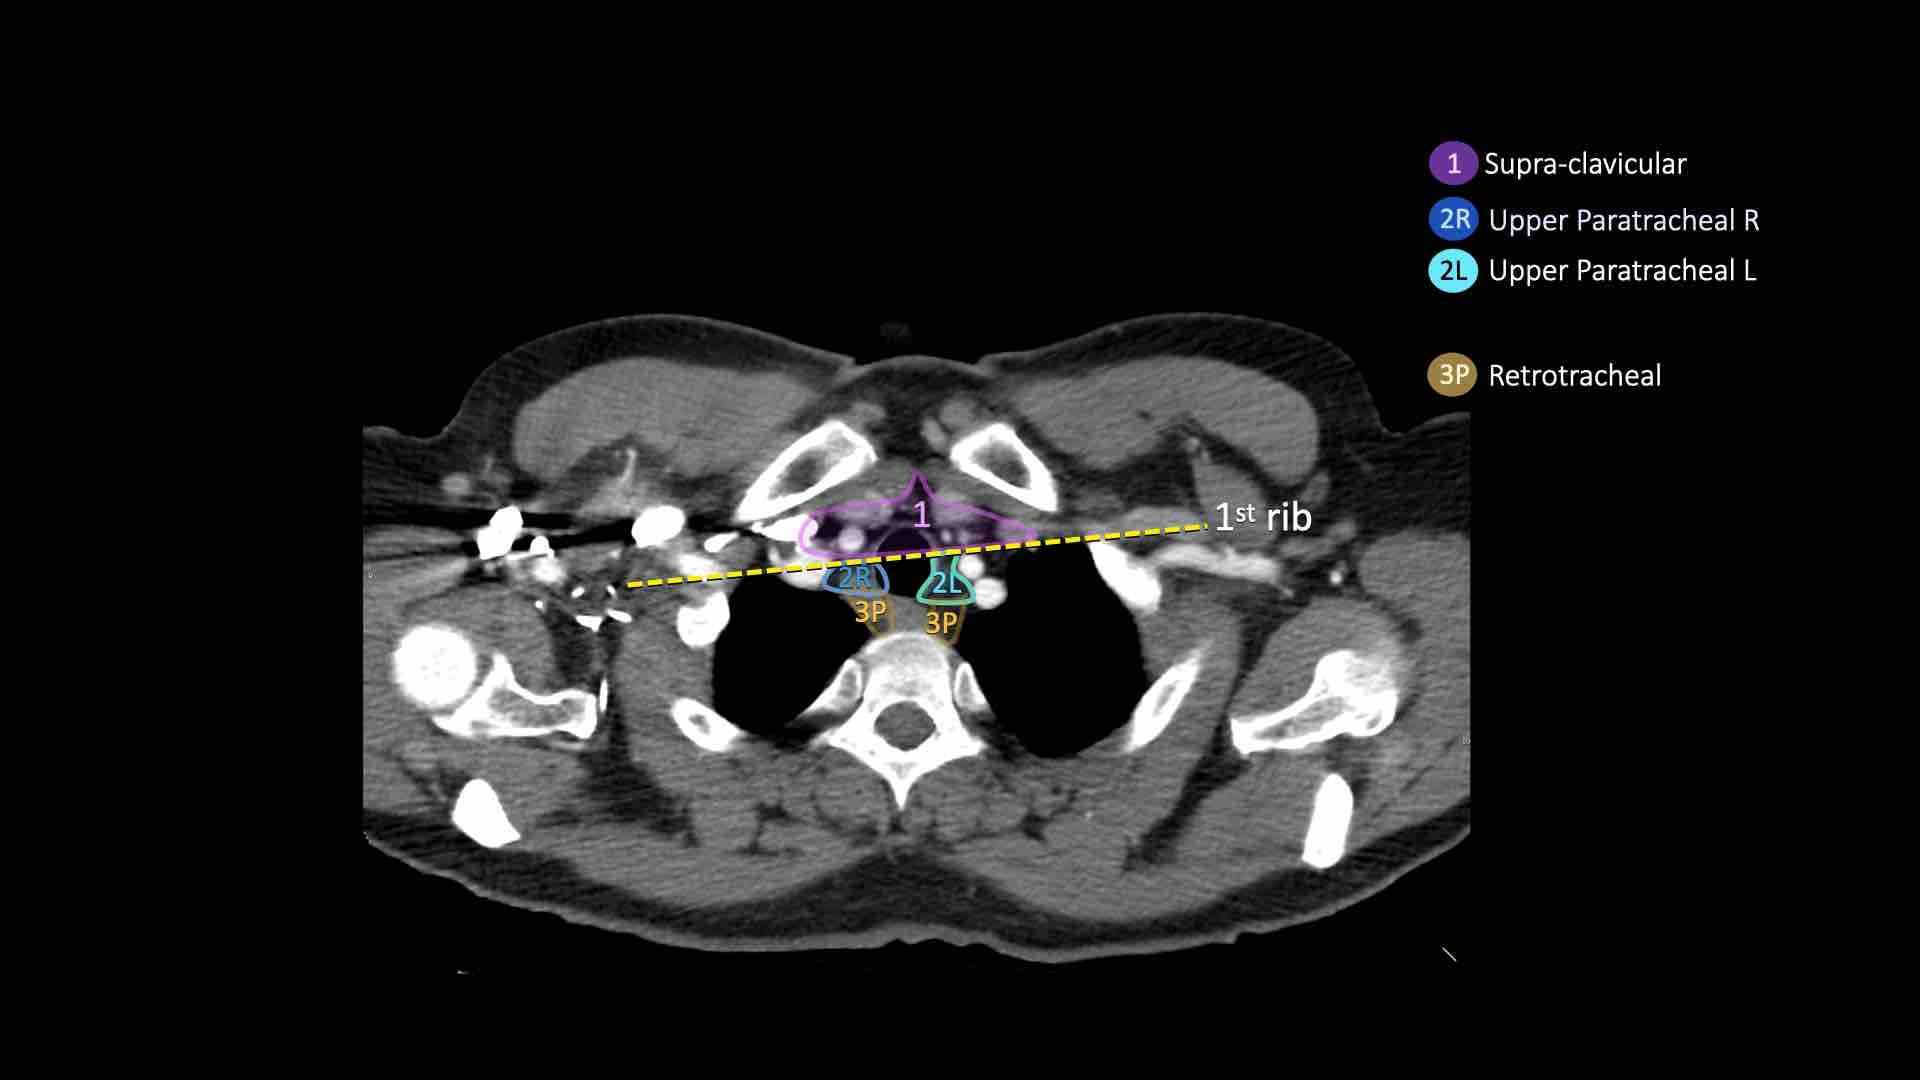

Giải phẫu CT cắt ngang

Nhấp vào hình ảnh để phóng to.

Sau đó cuộn qua các ảnh CT cắt ngang.

Hình ảnh do Bác sĩ Aurelia Fairise thuộc Viện Ung thư Lorraine tại Nancy cung cấp.

- Hạch bạch huyết khuyết ức có thể quan sát thấy ở mức này và phía trên mức này

- Cạnh khí quản trên: phía dưới xương đòn, bên phải nằm trên giao điểm của bờ dưới tĩnh mạch vô danh (tĩnh mạch tay đầu trái) với khí quản, bên trái nằm trên cung động mạch chủ

- Trước mạch máu và Sau khí quản: nằm trước các mạch máu (3A) hoặc trước cột sống (3P)

1. Hạch vùng thượng đòn

Bao gồm các hạch cổ thấp, thượng đòn và hạch khuyết ức.

Ranh giới trên: bờ dưới sụn nhẫn.

Ranh giới dưới: xương đòn và bờ trên cán ức.

Đường giữa khí quản là ranh giới phân chia giữa nhóm 1R và 1L.

2R. Hạch cạnh khí quản trên bên phải

Hạch nhóm 2R trải dài đến bờ bên trái của khí quản.

Ranh giới trên: bờ trên cán ức.

Ranh giới dưới: giao điểm của bờ dưới tĩnh mạch vô danh (tĩnh mạch tay đầu trái) với khí quản.

2L. Hạch cạnh khí quản trên bên trái

Ranh giới dưới: bờ trên quai động mạch chủ.